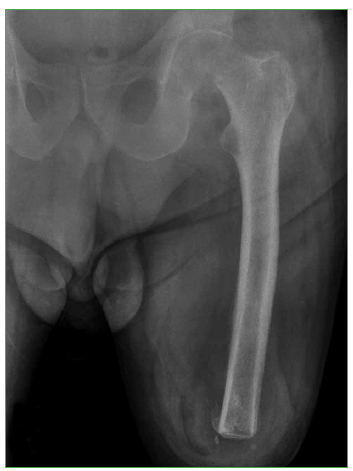

Reemplazo total de cadera en un paciente con amputación supracondílea homolateral